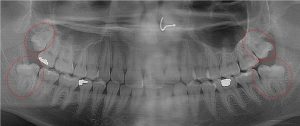

This 19 year old patient has all four 3rd molars present (circled). Only the upper left 3rd molar has fully erupted. The lower left 3rd molar is partially exposed and decaying while the lower right soft tissue impacted, both requiring extraction. Note the double crown on the upper right third molar.